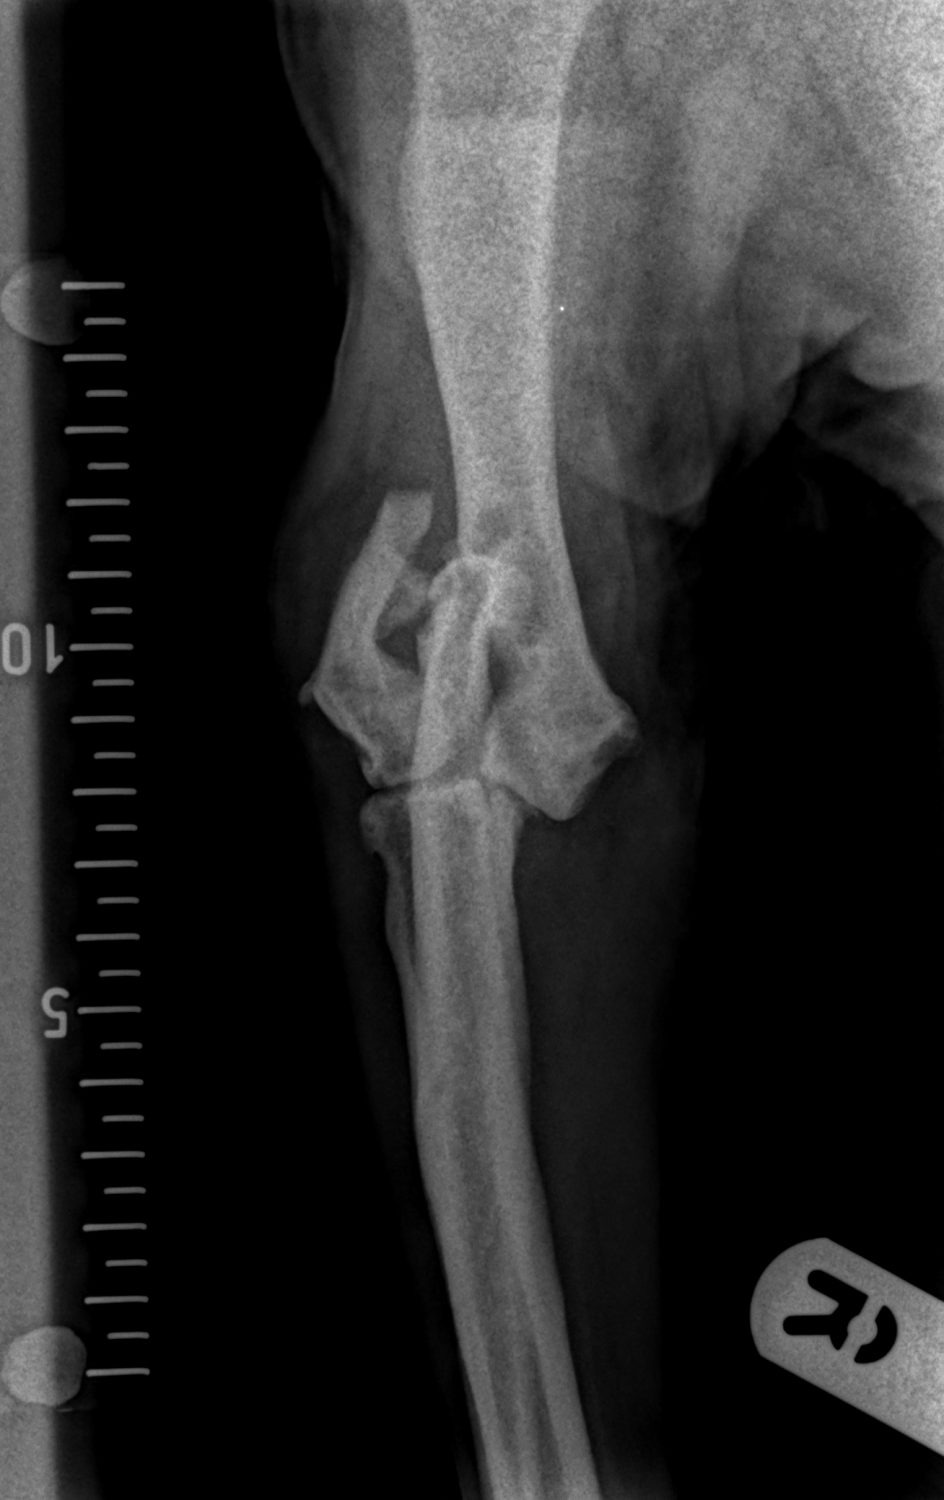

Chase is a twelve-year-old English Springer Spaniel, with a history of severe arthritis in his elbows, presented lame in the right elbow after sustaining an injury whilst jumping into the car. X-rays revealed a humeral intracondylar fissure that had fractured.

A humeral intracondylar fissure is a crack within the joint of the elbow; this weakens the joint and significantly increases the chance of fracture. It can affect many breeds but is especially common in English Springer Spaniels.